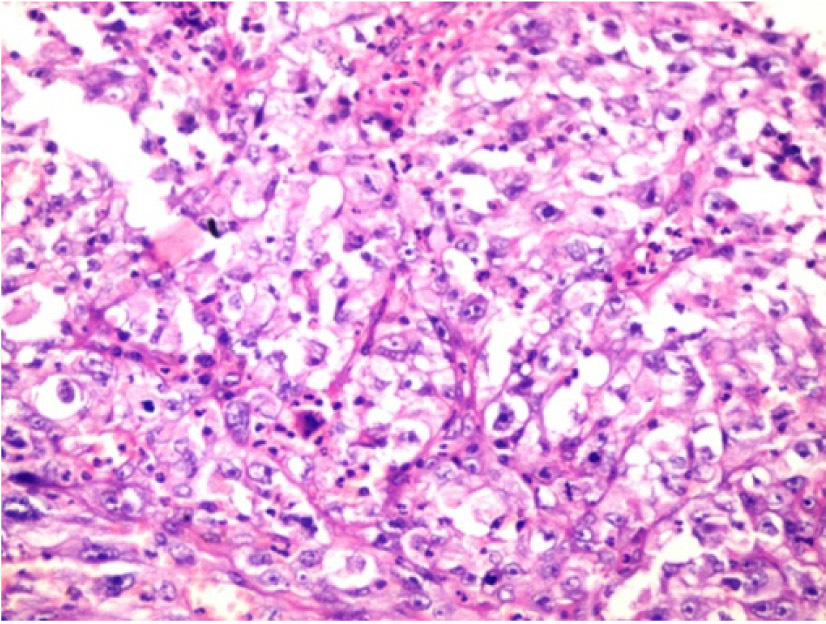

Under the impression of malignancy, an incisional biopsy was performed on the same day. Histopathological examination showed sheets of predominantly clear cells invading into underlying connective stroma [Table/Fig-2]. The clear cells were round to polygonal in shape consisting of clear cytoplasm with dysplastic features such as nuclear and cellular pleomorphism, hyperchromatic nucleus and abnormal mitotic figures suggestive of malignancy [Table/Fig-3]. Few areas were showing keratin pearl formation also [Table/Fig-4]. Tissue sections were subjected to histochemical and immunohistochemical (IHC) analysis to define the origin of tumour cells. The sections were negative for PAS, and mucicarmine stains ruling out the tumour of odontogenic and salivary gland origin. It also came out to negative for Oil red O (Fat stain) ruling out sebaceous neoplasm. IHC investigation revealed negative staining for Vimentin and S-100 hence, ruled out the possibility of malignancy of connective tissue and malignant melanoma also. Sections showed strong positive immunoreactivity for cytokeratins 8 and 18 (CK8 and CK18) [Table/Fig-5] suggestive of well differentiated SCC [Table/Fig-6].

Histopathologic picture (H& E; 40X) showing sheet of clear cells with dysplastic features.